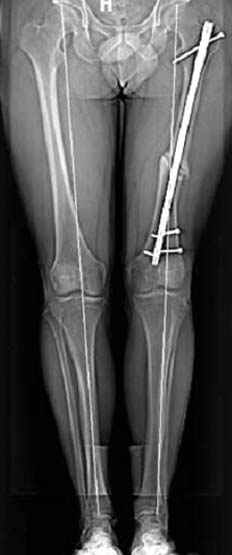

На рисунке N1 предоперационный план лечения ложного сустава шейки бедра- линия ложного сустава, угол и направление введения импланта, клиновидная остеотомия в градусах и миллиметрах, второй снимок после коррекции, расчет, на сколько удлиняется конечность и размеры импланта;

N3 рисунок окончательный снимок, после операции моя рентгенограмма должен выглядеть примерно как эта картина. На N4 снимке клин перед удалением; N5 послеоперации 3 нед.; N6 окончательная рентгенограмма.

пластическая модель; и коррекция бедра аппаратом Илизарова.

Узкий к-м канал - тонкий гвоздь- усталостный перелом дистальных винтов - развитие нестабильности и как ее результат остеолиз вокруг гвоздя - деформация анатомической оси бедра. Похоже, что я понял почему аппарат, а не новый гвоздь:-)